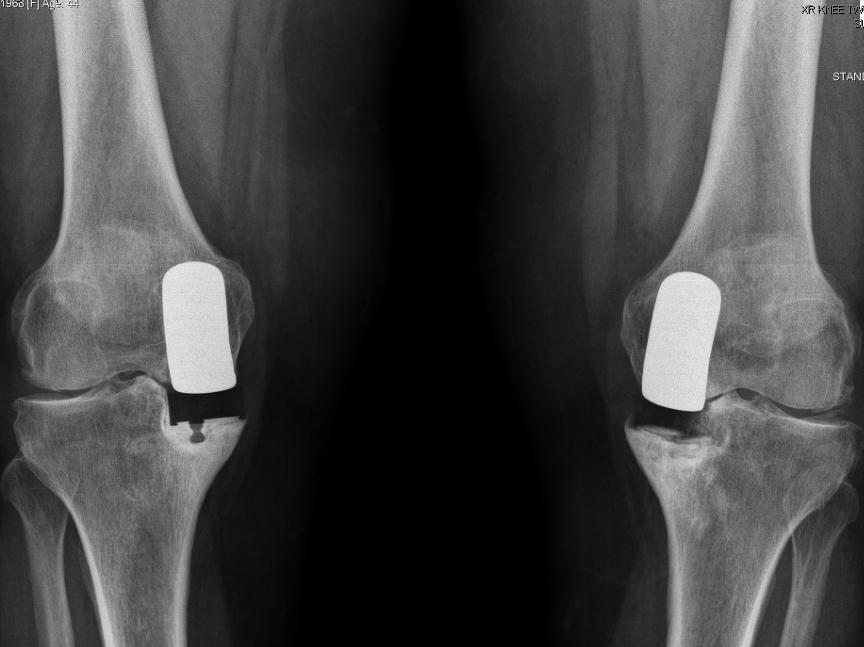

From www.researchgate.net

Anteroposterior radiograph of Patient B’s knee. knee Difference Between Unicompartmental And Total Knee Replacement Unicondylar knee replacement (ukr) and total knee replacement (tkr) are two major surgical options for medial knee oa. The aim was to determine if this. A partial or unicondylar knee replacement, as its name suggests, replaces only the affected compartment of the knee. Total knee arthroplasty (tka) and unicompartmental knee arthroplasty (uka) are both commonly used procedures for treating. Unicompartmental. Difference Between Unicompartmental And Total Knee Replacement.